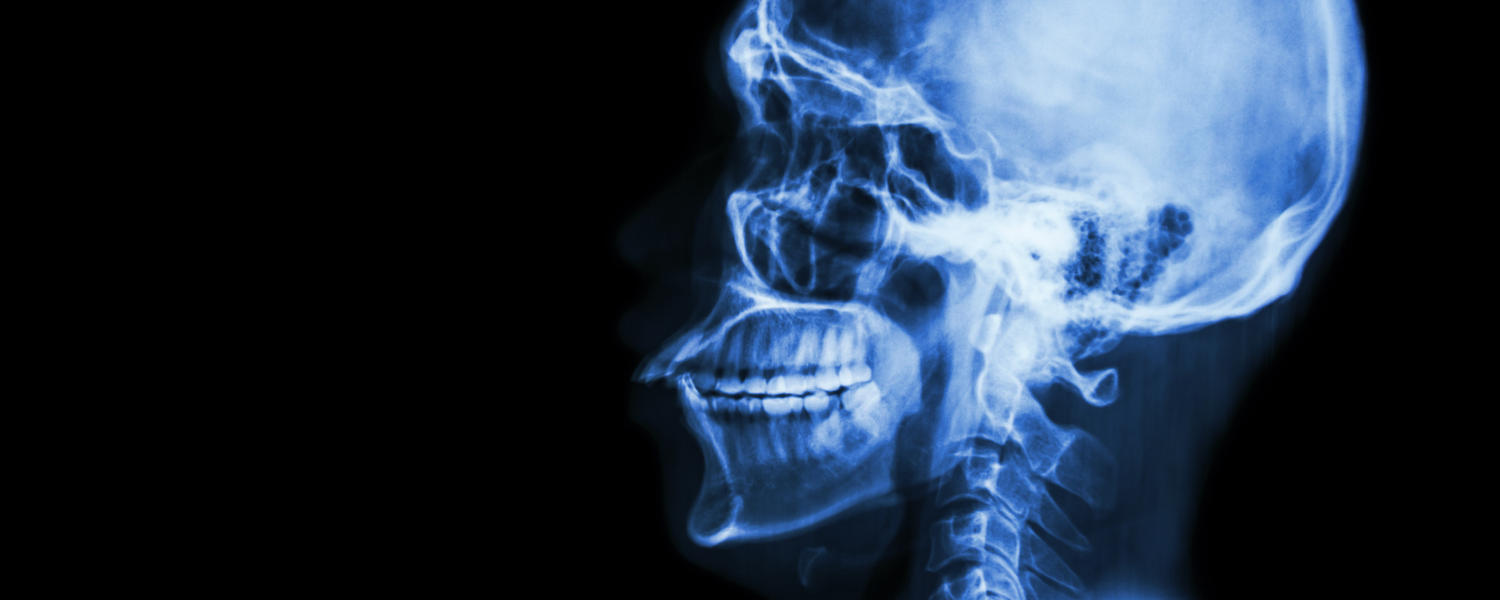

Head xray

Our section completed the first-ever immediate mouth, jaw, and facial reconstruction surgery for oral, head, and neck cancer. This “Jaw in a Day” reconstructive surgery combined free flap defect reconstruction with bone and soft tissue, immediate dental implants, and teeth. This treatment provides earlier return to function and minimizes the devastating effects of facial deformity secondary to head and neck cancer surgery.